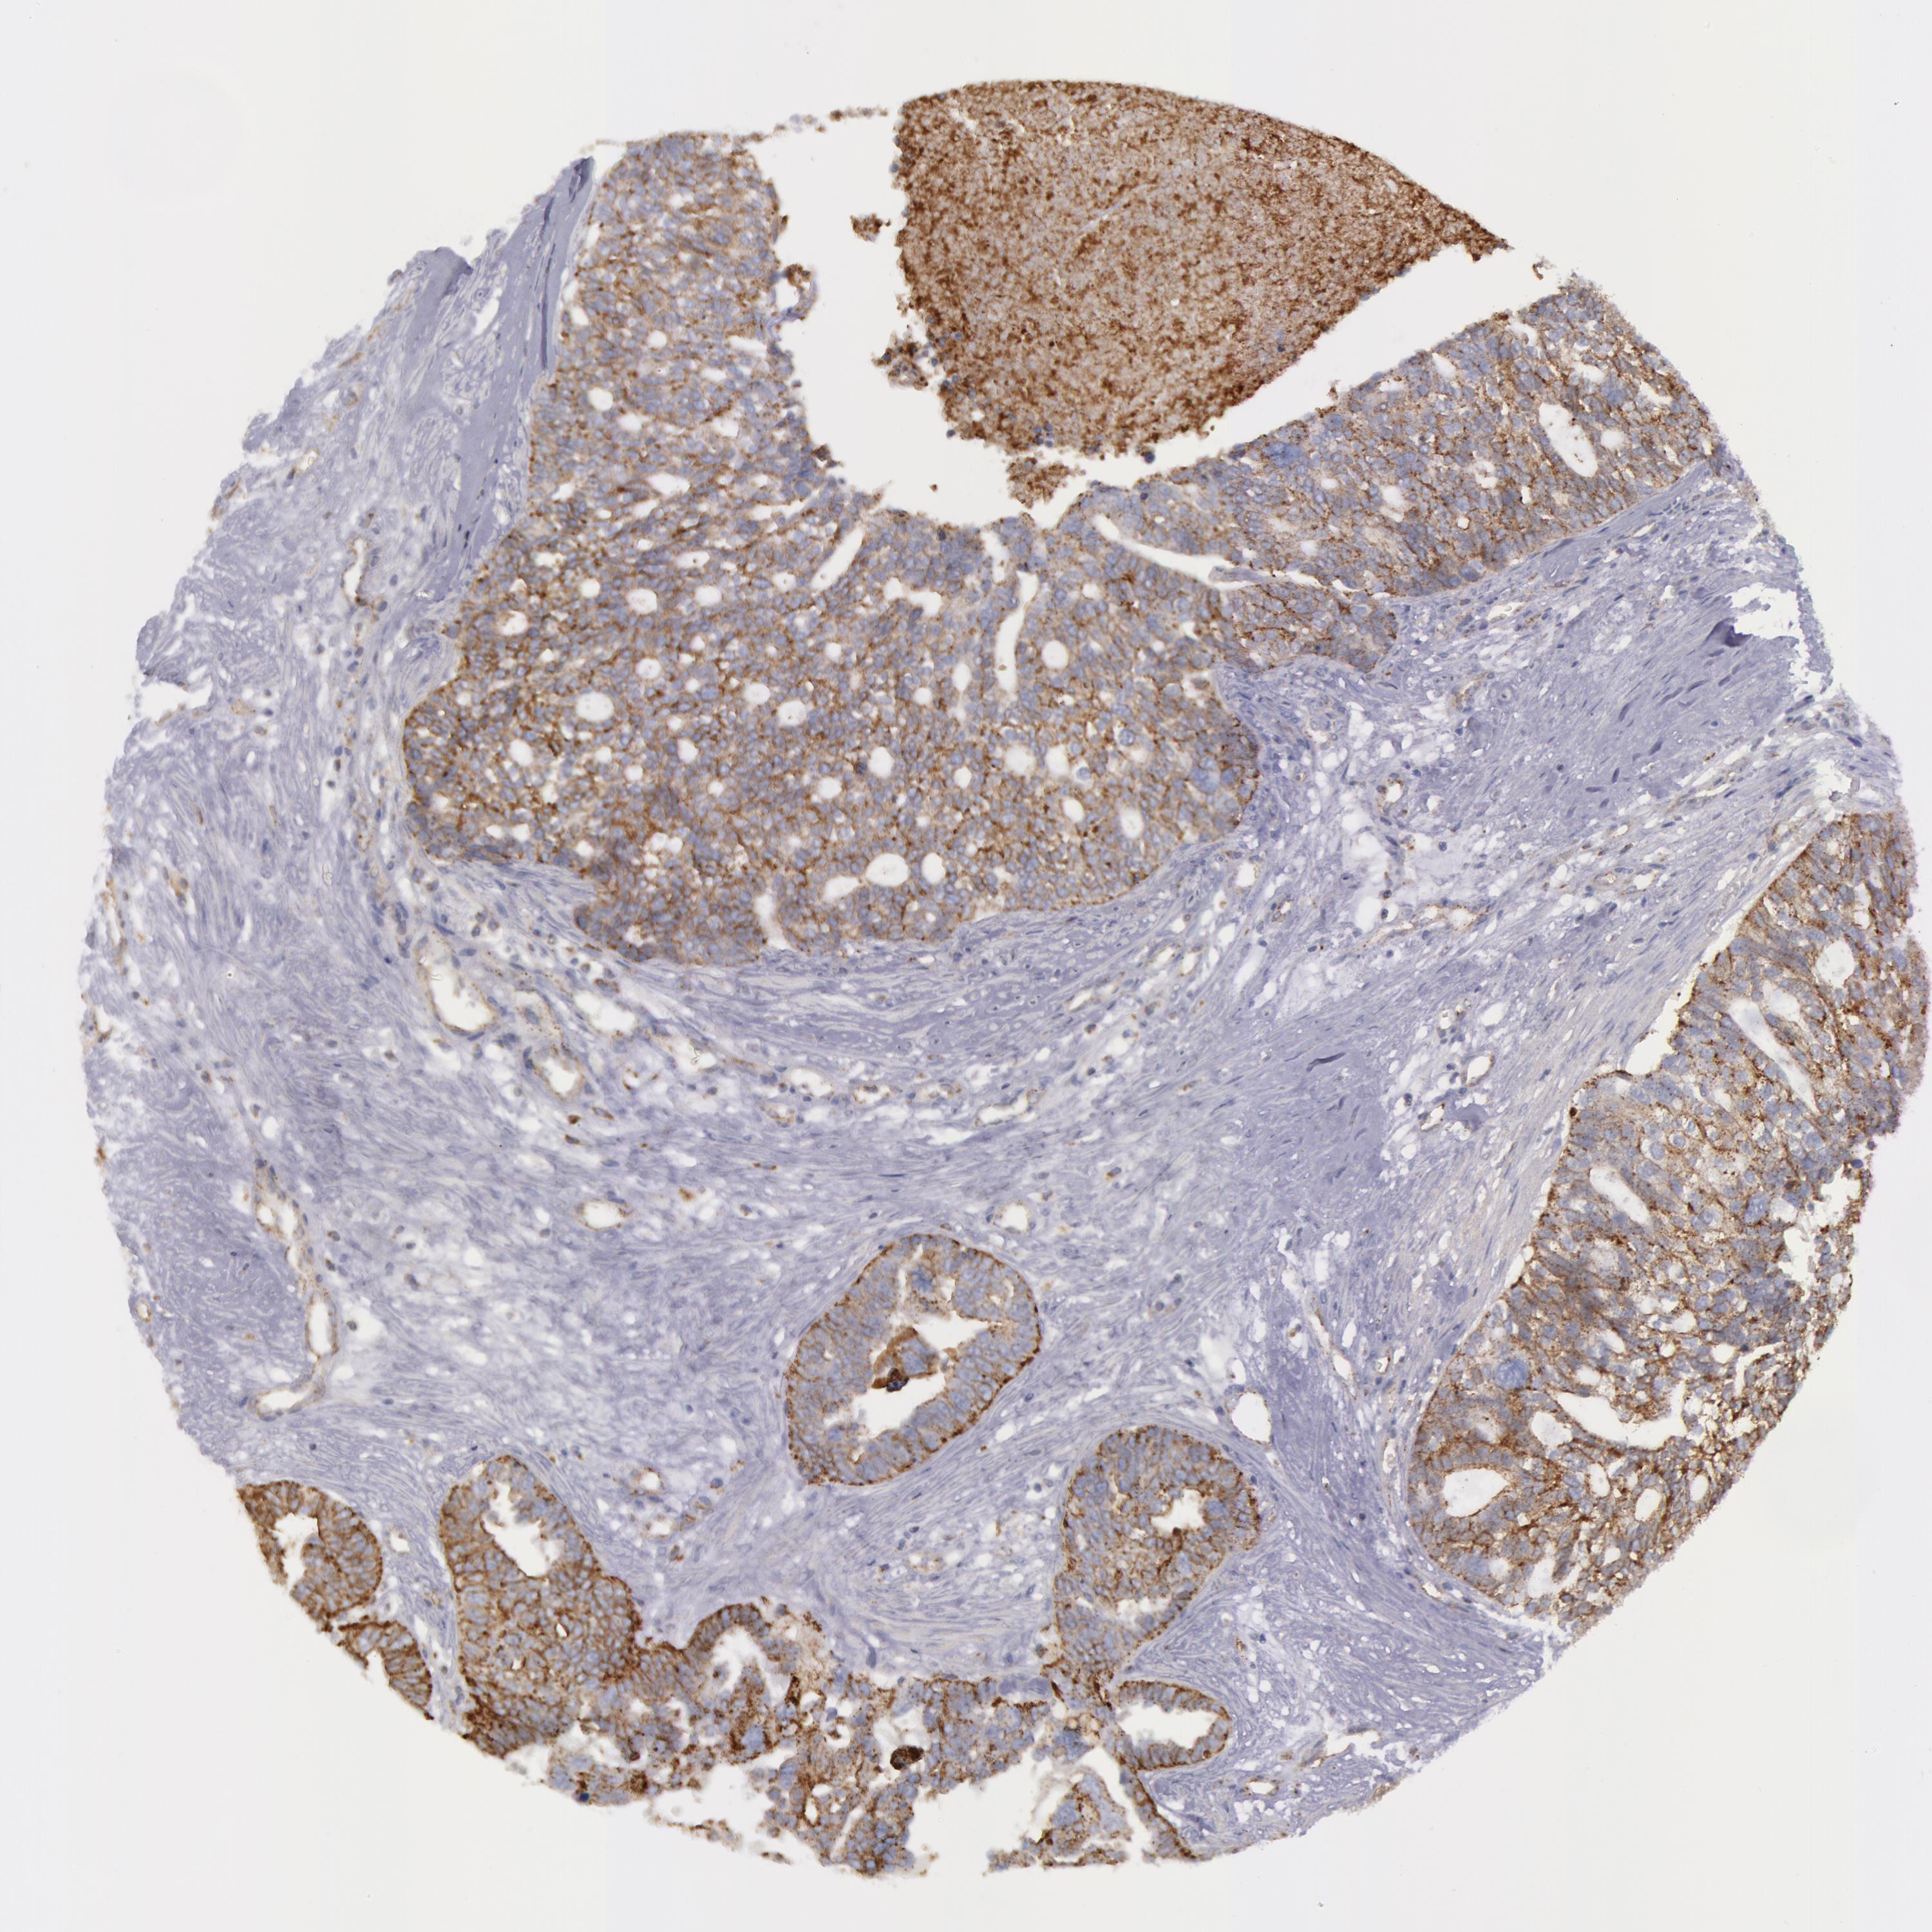

OVARIAN CANCER - Protein expressioni

A mouse-over function shows sample information and annotation data. Click on an image to view it in a full screen mode. Samples can be filtered based on level of antibody staining by selecting one or several of the following categories: high, medium, low and not detected. The assay and annotation is described here.

Note that samples used for immunohistochemistry by the Human Protein Atlas do not correspond to samples in the TCGA dataset.

Antibody stainingi

Antibody staining in the annotated cell types in the current human tissue is reported as not detected, low, medium, or high, based on conventional immunohistochemistry profiling in selected tissues. This score is based on the combination of the staining intensity and fraction of stained cells.

Each image is clickable and will lead to virtual microscopy that enables deeper exploration of all samples and also displays staining intensity scores, fraction scores and subcellular localization as well as patient and tissue information for each sample.

Antibody HPA001396

Antibody CAB004395

Cystadenocarcinoma, mucinous, NOS

Carcinoma, endometroid

Cystadenocarcinoma, serous, NOS

Carcinoma, NOS